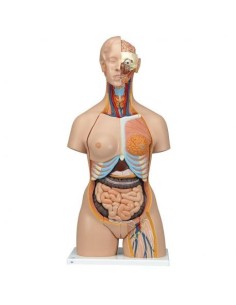

Scopri il Mondo dell’Anatomia con Modelli anatomici di Precisione

Benvenuto su Tuttoanatomia.it, il portale di riferimento in Italia per l’acquisto di modelli anatomici, poster, lettini portatili, simulatori medici e letteratura specialistica. Con i nostri modelli anatomici di 3B Scientific ed Erler Zimmer, leader mondiali nel settore, offriamo un’esperienza di apprendimento senza pari.

Modelli Anatomici Dettagliati per Ogni Necessità

Dal cranio in 22 parti con incastri magnetici ai modelli di colonna vertebrale, da quelli di articolazioni a quelli di cuore, ogni pezzo della nostra collezione è progettato per un’immersione totale nello studio dell’anatomia umana. I nostri modelli, realizzati tramite scansioni di ossa vere, garantiscono un’esperienza tattile autentica e una fedeltà di peso quasi identica agli originali.

Strumenti Didattici Innovativi per l’Educazione e la Pratica Medica

Essenziali per studenti e professionisti, i nostri modelli anatomici sono strumenti didattici che permettono di osservare le strutture anatomiche con precisione, eliminando la necessità di dissezioni o studi invasivi. Sono inoltre utili per spiegare ai pazienti le patologie, rendendo la comunicazione più efficace e risparmiando tempo prezioso.